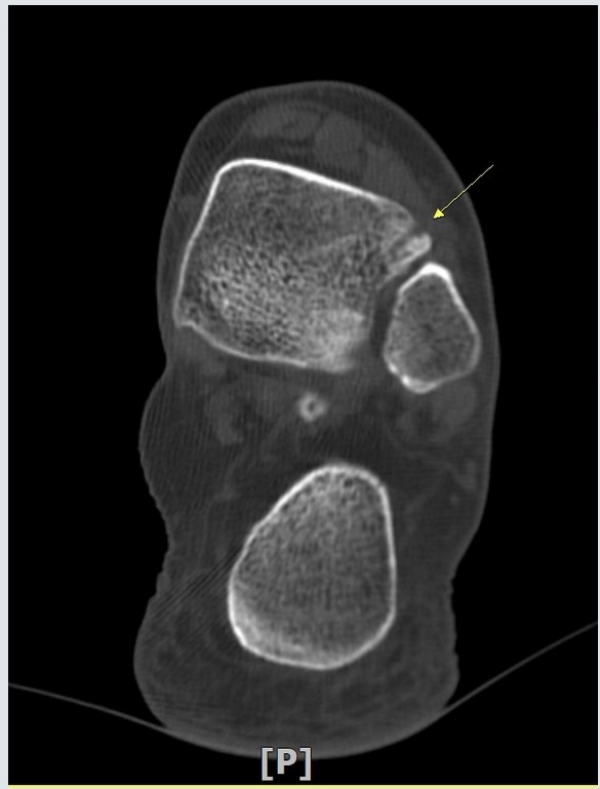

¾Õ°æ°ñºñ°ñÀδë Á¾´Ü¸é°Ë»ç¿¡¼­ °æ°ñºñ°ñÀδëÀÇ  Àú¿¡ÄÚ  ºÎÁ¾ ¹× ÀδëºÎÂøºÎ °æ°ñÀÇ

°ß¿­°ñÀýÀÌ  °üÂûµÊ(»çÁø 2, 3, 4)